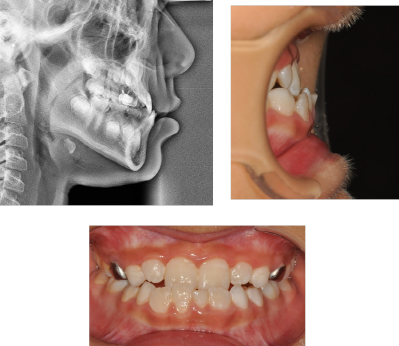

환자분께서는 아이의 치아가 반대로 물려서 내원을 해주셨습니다.

반대교합과 함께 아래턱이 위턱보다 더 나와있는

주걱턱이 함께 있어 성장교정을 진행했습니다.

그러면 이렇게 반대교합도 해소하고,

위 아래 턱의 조화도 맞출 수 있게 되었습니다.